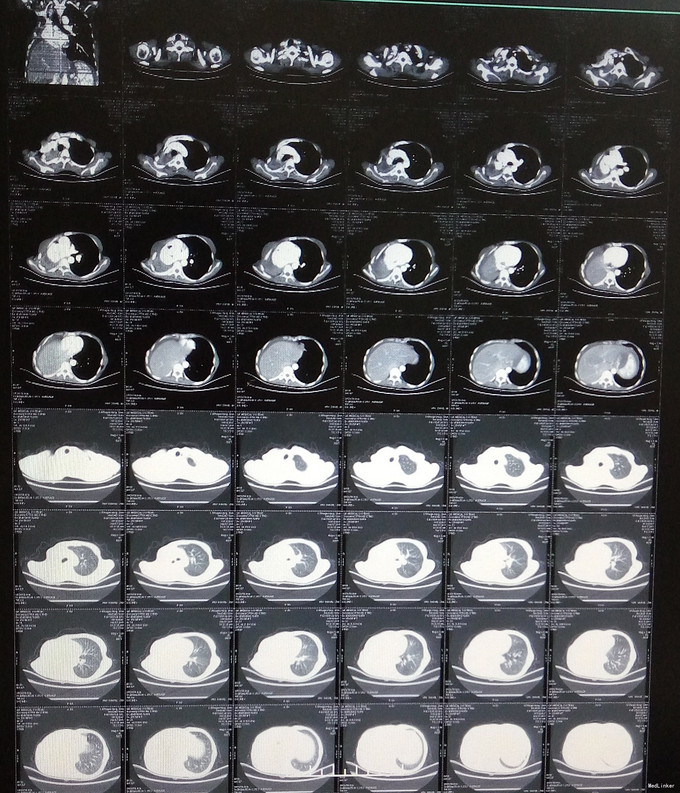

查体:生命体征平稳,腹部饱满,无腹壁静脉曲张,腹韧,无压痛、反跳痛及肌卫,移动性浊音(+),肠鸣音6次/分。 辅助检查:胸部CT:右肺缺如。血钾:3.24mmol/l(见图1-2)。